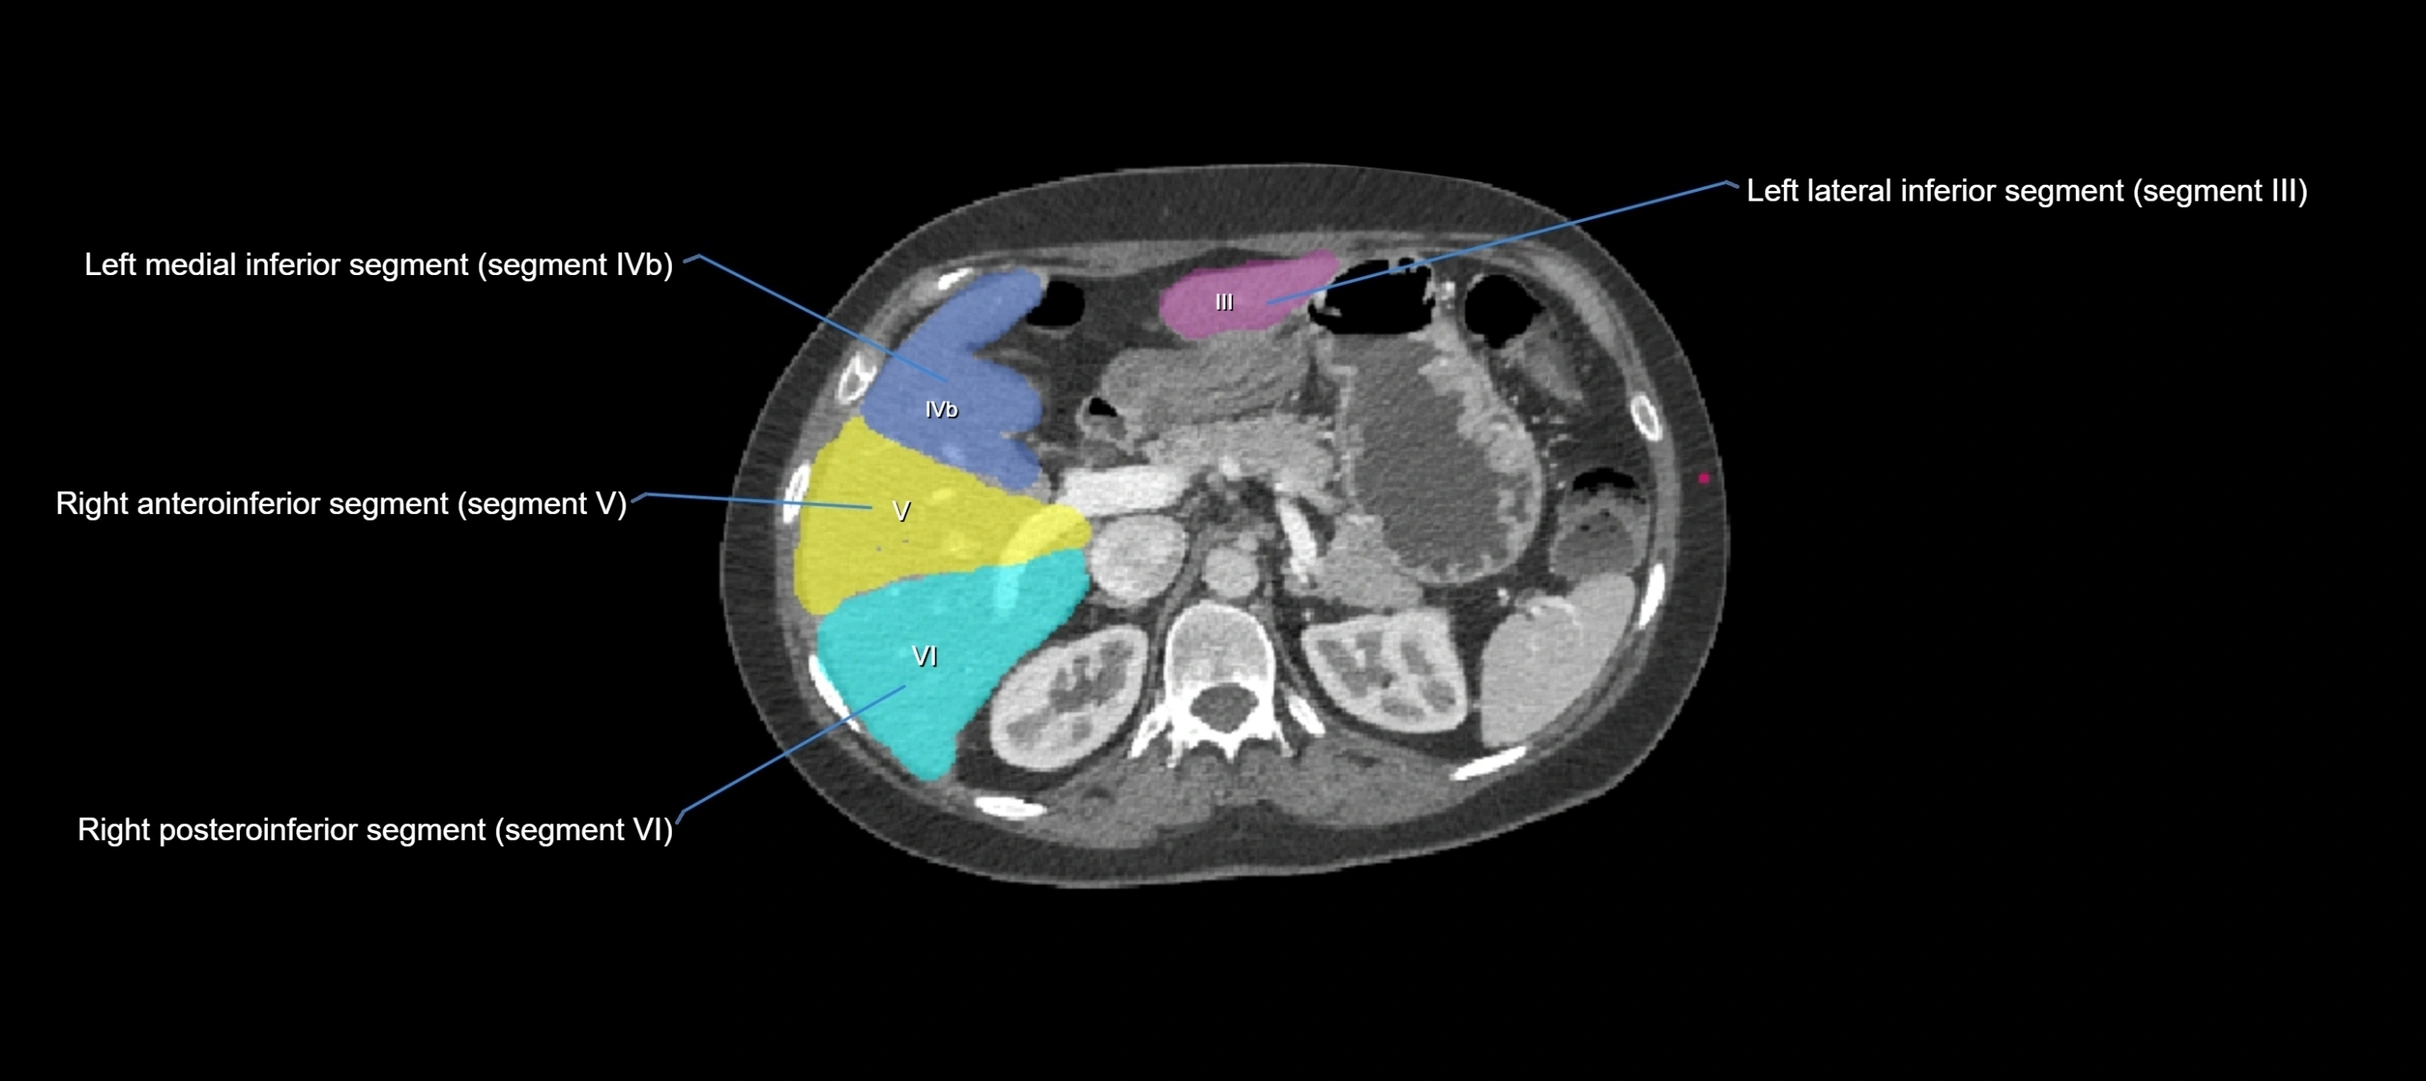

CT Image

image